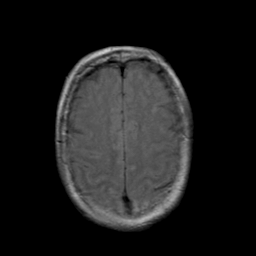

Stroke: proton density-weighted MR #2 -- Slice #19

[Home][Help][Clinical] Slice 19